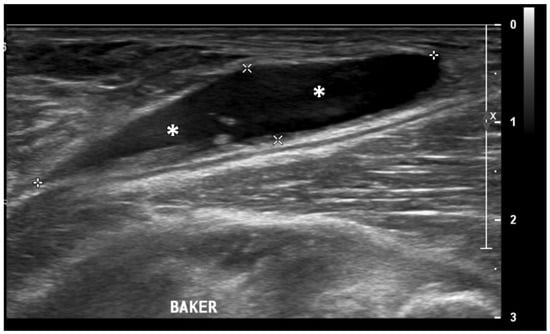

Figure 3.

Ultrasound image (Power-Doppler) longitudinal, lateral suprapatellar view showing synovial inflammatory foci with inflammatory hyperemia (arrow).

Figure 4.

Ultrasound image (B-mode) longitudinal posterior view in the medial aspect of the popliteal fossa showing large fluid collection (asterisks) within the medial head of the gastrocnemius and the semimembranosus tendons’ sheet (Baker’s cyst).